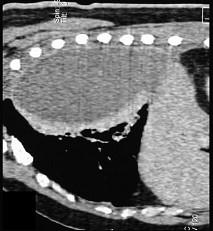

男,59岁,呼吸困难,胸痛,有发热,请结合CT图像选择最可能的诊断 ( )A、肺囊虫病B、肺癌C、肺脓肿D、大叶性肺炎E、脓胸

问题 男,59岁,呼吸困难,胸痛,有发热,请结合CT图像选择最可能的诊断 ( )

选项 A、肺囊虫病 B、肺癌 C、肺脓肿 D、大叶性肺炎 E、脓胸

答案 E